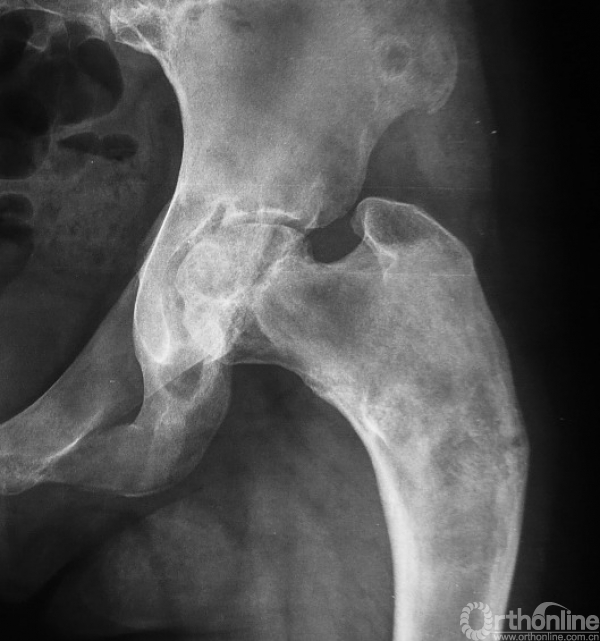

本病女性多见,男女发病率约为1.2:3,多在10岁左右发病,主要症状为轻微疼痛,局部肿胀及压痛。因症状轻微往往被忽略,多数病例是在以后查体或发生病理骨折时才被发现,骨折时疼痛可突然加重,肢体功能障碍,但骨折很少移位(图1),由于受累骨的坚固性受到明显影响,肢体可出现弯曲畸形,发生于股骨近端的常形成髋内翻,被称为“牧羊拐畸形”(图2)。

图2 牧羊拐畸形